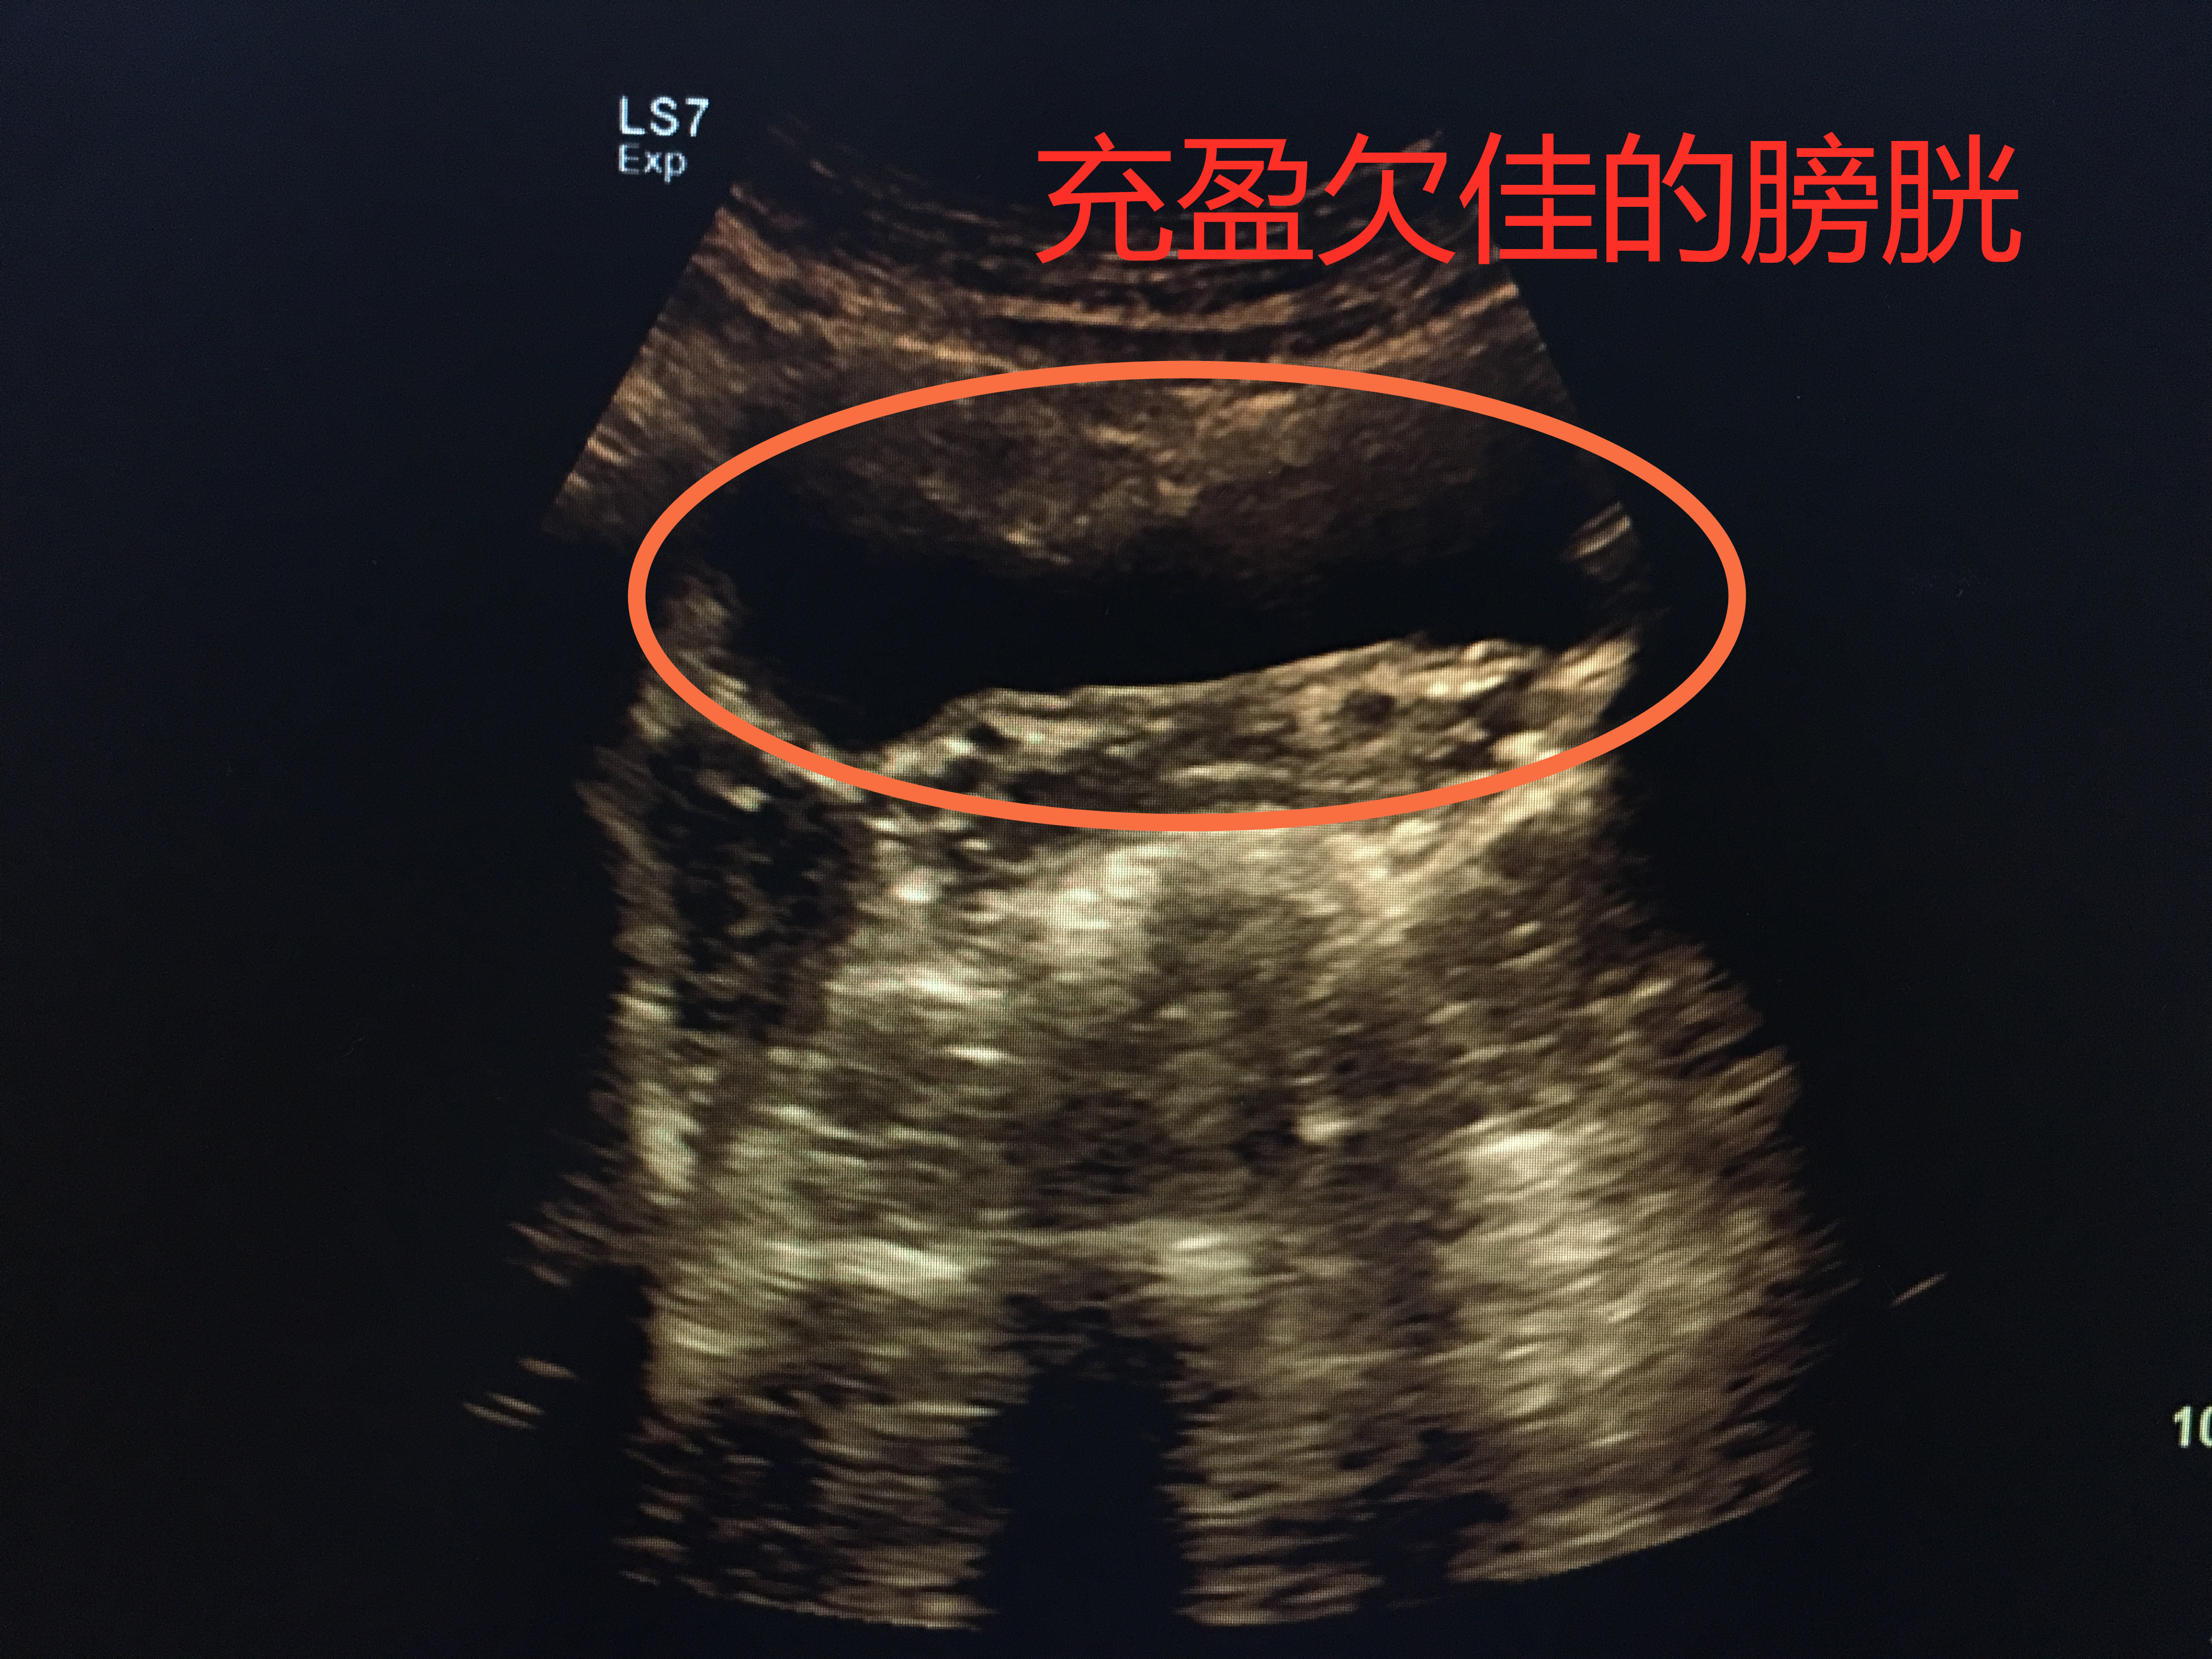

膀胱B超:让你憋尿就努力憋住吧

下腹痛、小便痛或者尿频尿急等情况的时候,医生一般会建议做一个泌尿系彩超检查,其中就包括了膀胱B超检查,这是后就有一件必须完成的事:憋足够的尿。

憋尿欠佳,膀胱欠充盈

膀胱就像一个皮球,当你往里面打足气时,皮球便充分撑开;而当打的气不够时,皮球就瘪着。所以,当你憋尿充足时,膀胱充盈起来,把每个角落都撑开,检查时便一览无遗;当憋尿不够,充盈欠佳时,局部可能皱褶起来,隐藏病灶。所以,下次医生让你憋尿的时候,就努力的憋吧。